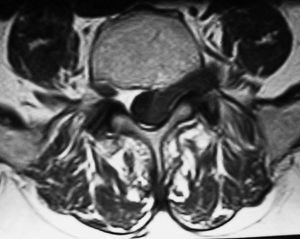

Fig. 1--RM secuencia TSE pT2. Corte axial. Lesión en canal, foramina y espacio extraforaminal con "morfología en reloj de arena". La raíz nerviosa correspondiente se aprecia separada de la hernia en el espacio extraforaminal. Respecto al músculo psoas la periferia de la lesión es discretamente hiperintensa y su centro isointenso.

Varón de 77 años con lumbociatalgia izquierda de tres meses de evolución. Se practica tomografía computarizada (TC) y resonancia magnética (RM) de columna lumbar.